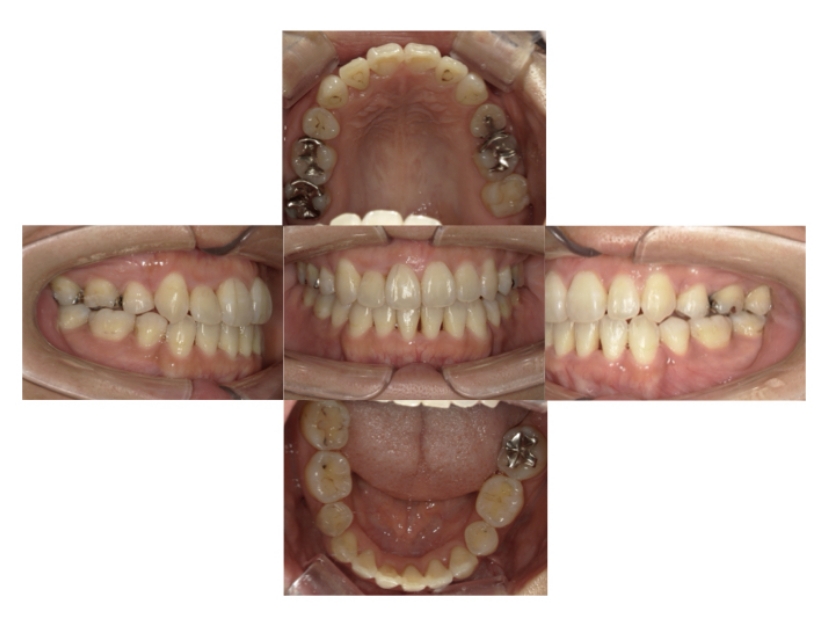

BEFORE

AFTER

上下顎叢生(上下の前歯のガタガタ)のケースです。

装置はラビアル(上下表側)で、上下顎の小臼歯を4本抜歯を行っています。抜歯したスペースを使って、上下の前歯の後方移動と叢生(ガタガタ)の改善を行っています。

主訴 八重歯を治したい。

年齢・性別 25歳 女性

お住まいの地域 神奈川県川崎市

治療方針 抜歯スペースを利用して上前歯の叢生(ガタガタ)の改善

抜歯部位 上下顎左右第一小臼歯

使用装置 ラビアル(上下表側)、顎間ゴム

治療期間 1年11か月

治療回数 16回

リテーナー クリアリテーナー